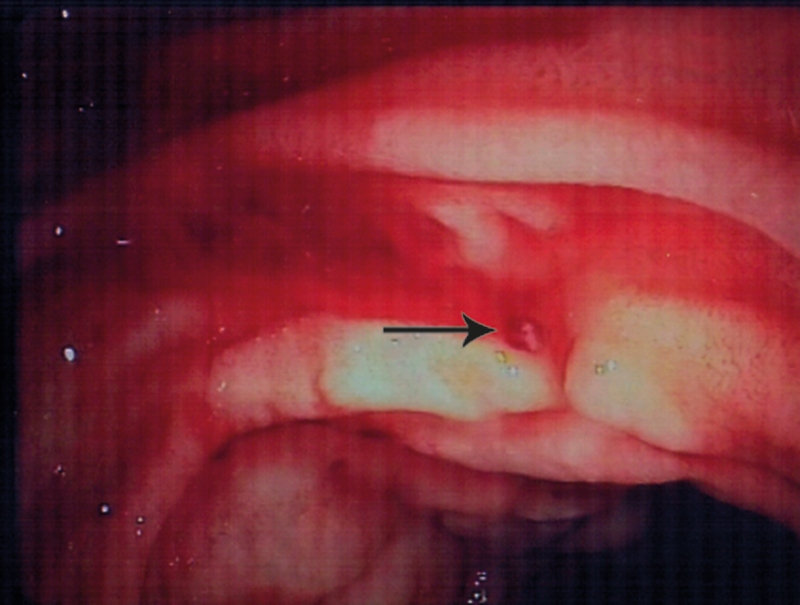

Pasientens hemoglobinnivå var stabilt på 7,7 g/100 ml til dagen etter (dag 3) og fortsatte å stige utover dagen (8,4 g/100 ml) uten ny tilførsel av blod. Det var ingen avføring/melena morgen/ettermiddag. Ny gastroskopi (nr. 4) bekreftet at blødningen var stanset (fig 3). På grunn av opplysninger i sykehistorien om mulig lettgradig hemoragisk diatese ble det konferert med hematolog, som anbefalte å ta von Willebrand-prøver i rolig fase. Det ble også konferert med revmatolog, som ikke fant holdepunkter for vaskulitt. En CT-undersøkelse av abdomen avdekket kun lett ødem i duodenalveggen.